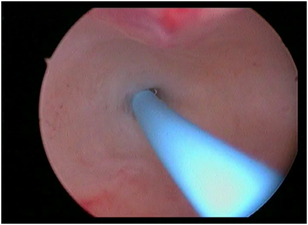

4) Asherman (गर्भाशयाचा आंतरभाग चिकटून बसणे) -

गर्भाशयाला जंतूसंसर्ग झालेमुळे गर्भाशयाची पोकळी आतून चिकटली जाते. त्यामुळे अंगावरुन फार कमी जाणे / फक्त डाग पडणे व गर्भधारणा न होणे अशा अनेक अडचणी निर्माण होतात. जर आपण ही पोकळी व्यवस्थित केली तर त्याचे फायदे होतात. घोडके हॉस्पिटलमध्ये अशा प्रकारच्या शस्त्रक्रियेमुळे बऱ्याच पेशंटना त्याचा फायदा झालेला आहे.

ashermanbeforeoperation

ऑपरेशनपूर्वी